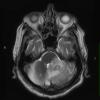

NEOPLASMS (HEMATOLYMPHOID)

Lymphoma, primary